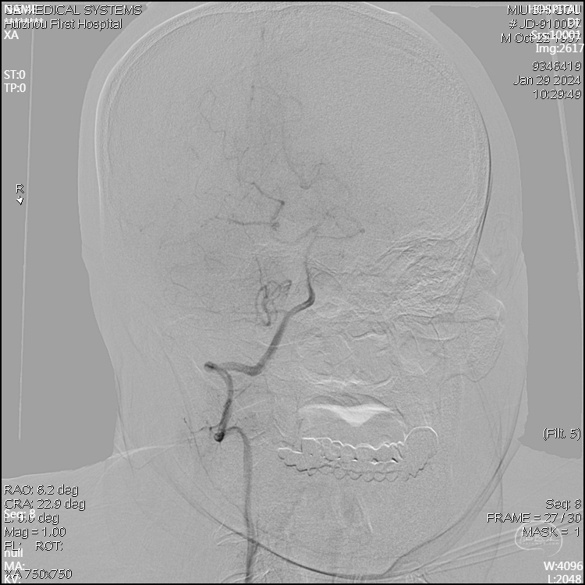

急诊DSA未见畸形血管。

右侧颈外侧位